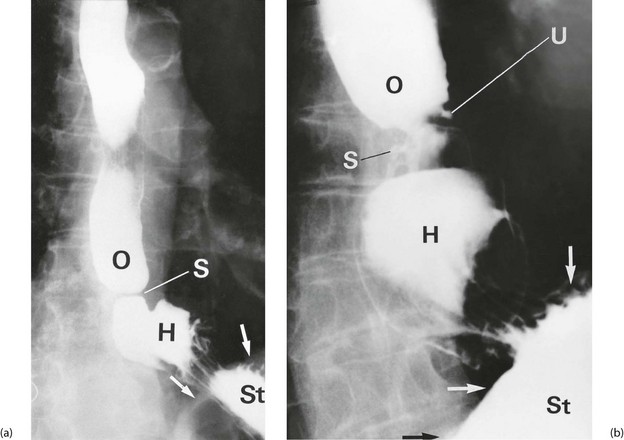

Contrast radiography of the upper gastrointestinal tract is used largely to determine swallowing function, to define anatomy, particularly with large hiatus hernias, and to give an idea of the effectiveness of gastric emptying. It involves the patient swallowing barium suspension (barium meal). During the investigation, the patient is tilted and rolled in various directions to demonstrate the whole region of interest. Effervescent tablets are given to produce gaseous distension of the stomach and duodenum and spread the contrast in a thin, even layer over the mucosal surface. This standard double contrast technique improves the imaging of mucosal detail.

All peptic disorders of the oesophagus are associated with reflux of gastric contents. These disorders range from mild reversible inflammation, through moderate acute inflammation with superficial ulceration (reflux oesophagitis), to severe persistent inflammation which may lead to fibrotic scarring and stenosis (see Fig. 21.3) and sometimes chronic peptic ulceration. In many patients, reflux is associated with hiatus hernia (see Ch. 22).

On gastroscopy, reflux oesophagitis is characterised by mucosal reddening and, in more severe cases, by typical linear superficial ulceration (see Fig. 21.4). Peptic strictures occur in the distal oesophagus and are usually located just above the oesophago-gastric junction, which itself often lies above the diaphragm because of inflammatory shortening of the oesophagus. The normal oesophago-gastric junction is about 40 cm from the incisor teeth when seen on endoscopy. Specialised intestinal metaplasia, dysplasia and carcinoma must be excluded by biopsies because the visual appearances may not be characteristic. Occasionally, a deep chronic ulcer occurs in the lower oesophagus; this looks and behaves like an often linear gastric or duodenal ulcer. When squamous oesophageal epithelium is repeatedly damaged by reflux, it may be replaced by metaplastic columnar epithelium. This is known as Barrett's oesophagus and there is strong evidence that it predisposes to malignant change. If found, it should be biopsied to exclude dysplasia. When dysplasia is severe, there is about a 1% annual risk of malignant change and endoscopic resection or surgery is necessary. Standard protocols are usually employed for surveillance of Barrett's oesophagus with repeated endoscopy every 2–3 years.